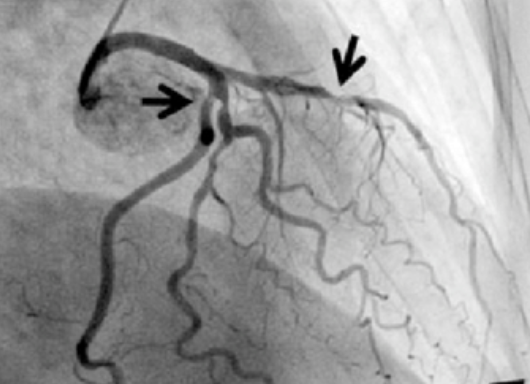

중년 심정지의 가장 핵심적인 원인은 관상동맥질환입니다. 관상동맥 내 죽상경화가 진행되면 혈관 내강이 좁아지고, 혈전이 형성되면서 심근으로 가는 혈류가 갑자기 차단될 수 있습니다. 이로 인해 급성 심근경색이 발생하며, 심실세동이나 심실빈맥 같은 치명적 부정맥이 동반되면 즉각적인 심정지로 이어질 수 있습니다.